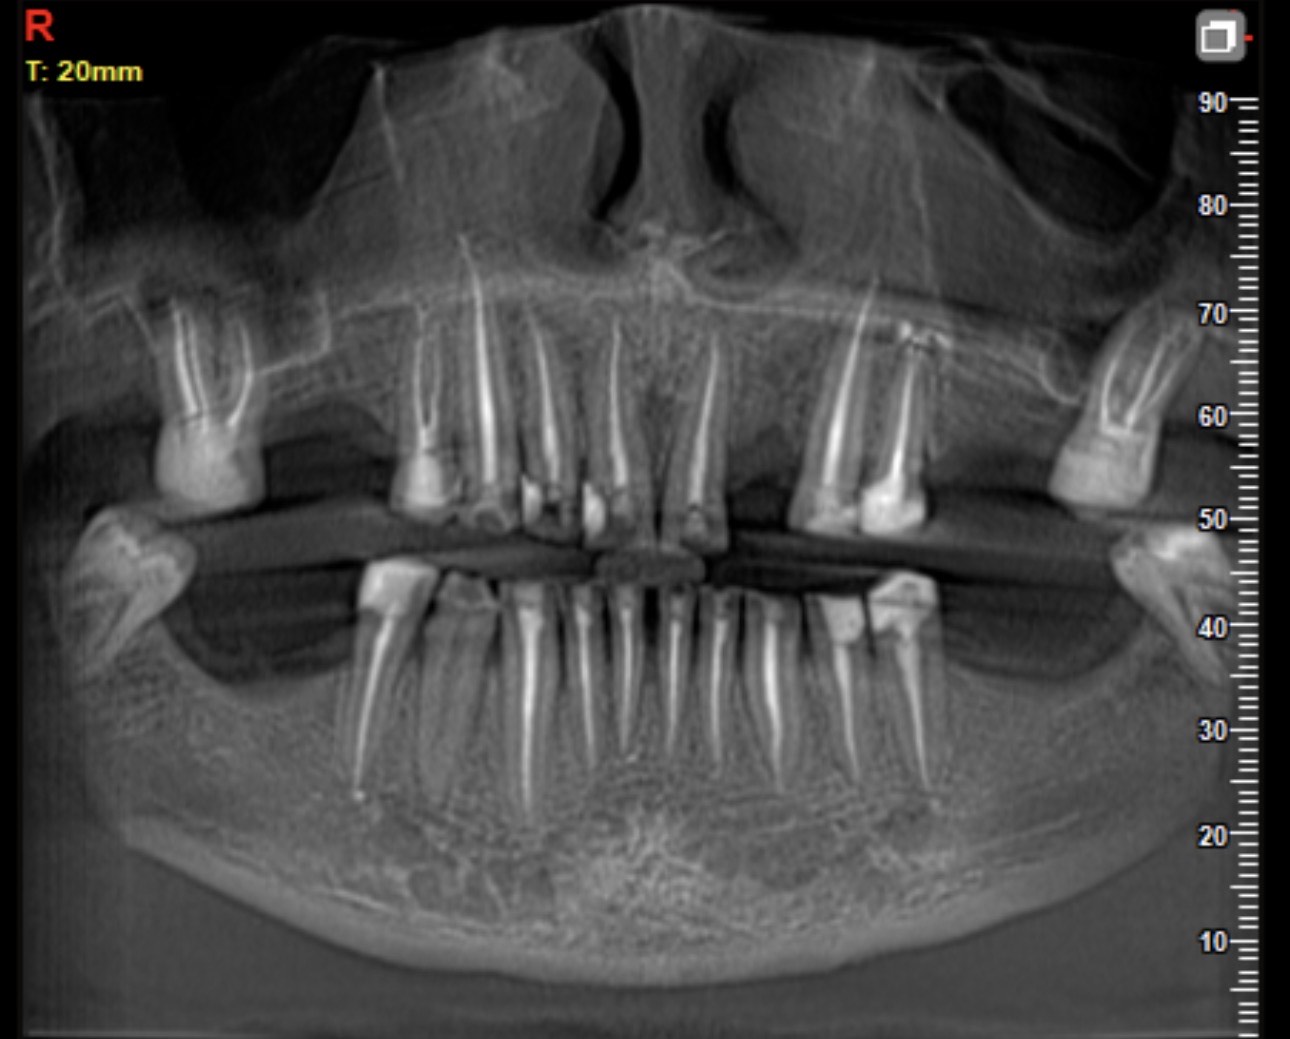

Pas trajtimit u realizua sërish ekzaminimi 2D dhe 3D scanner, për të verifikuar saktësinë e punës, stabilitetin okluzal dhe harmoninë funksionale e estetike të rehabilitimit.